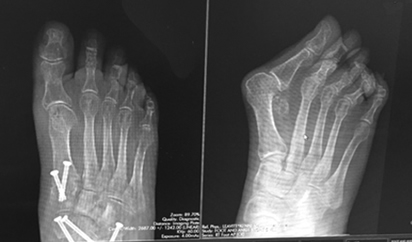

At my first appointment when Dr. Leavitt examined my feet and viewed the x-rays, he was very confident he could fix my problems. I placed my trust in his ability because he's done hundreds of these operations. I was a little nervous due to my age, but he was very reassuring.

The first operation corrected my left foot in December, 2015 - a triple arthrodesis (which involves fusing 3 joints in the back of the foot and ankle) and a bunionectomy to fix the bunion. Also he lengthened my achilles tendon. Dr. Levitt performed the same surgery on my right foot 2 years later.